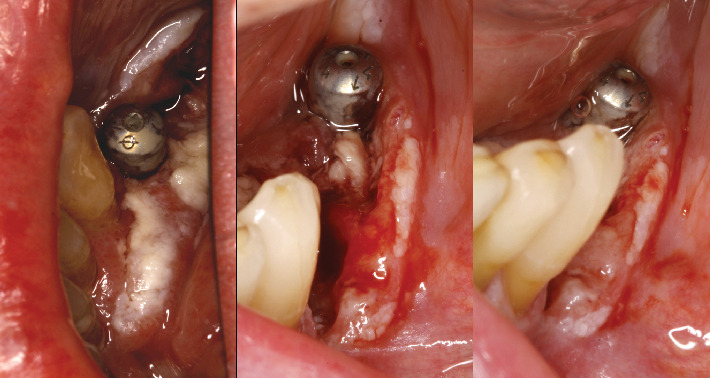

口腔扁平苔藓患者有时会发展为恶性过程,发展为口腔鳞状细胞癌或其他类型的癌症。密切监测病变和早期诊断对提高患者生存率非常重要。一旦进行了癌症治疗,除了解决美学后遗症外,恢复咀嚼和发音功能的治疗选择也很重要。在目前的临床病例中,我们展示了一位接受治疗并随访了很长一段时间的患者,她的癌症和随后的种植体康复。

Patients with oral lichen planus can sometimes develop malignancy of the process and develop oral squamous cell carcinoma or another type of cancer. Close monitoring of the lesions and early diagnosis is important to increase patient survival. Once cancer treatment has been performed, the therapeutic options for restoring masticatory and phonatory function, in addition to resolving the aesthetic sequelae, are important. In the present clinical case, we show a patient who was treated and followed over a long period of time for both her carcinoma and her subsequent rehabilitation with implants.